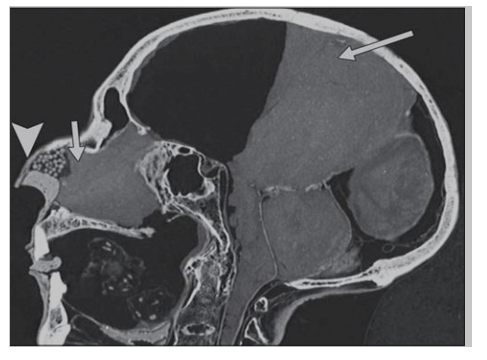

Figure 4: A CT scan of Merneptah’s head on (A) the axial brain window shows a big hole in the back of his skull (posterior right side of the skull), (B) the volume rendering technique shows the hole in the skull was filled with some material for restoration, and (C) the sagittal brain window shows the bulk of intracerebral contents located more anteriorly. The CT scan source: Sahar Saleem’s published paper in the American Journal of Roentgenology in April 2013.

But the salt that was found is not a Natron or table−salt, but a sea− salt which contains minerals and it looks darker than table salt. Natron is sodium carbonate, sodium bicarbonate, sodium chloride, and sodium sulfate. Sea salt is composed of sodium chloride mainly with salt from elements like; calcium, magnesium salts of chloride, potassium, sulfate. And more other elements in small amounts like; bicarbonate, bromide, borate, strontium, fluoride, silicate, iodide. What Bucaille found is a sea−salt, not Natron. Maurice also, come to the conclusion that Merneptah is the Moses’s Pharaoh or the exodus Pharaoh in his book. In the Arabic translation of his book, when he said “Mernpetah is the pharaoh.” (page 294 le bible le quran la science, The Arabic version). Maurice himself disagree with Sahar Saleem when he said “both mummies were studied and undergo the same tests, both Ramses II and Merneptah (page 304). In addition, Maurice agrees with Sahar when he found that merneptah fits more to be the pharaoh of exodus and he said “this pharaoh whether he died drowning according to biblical narratives, or because of the very severe traumas that proceed the sea drowning him or both together” (page 304). Meanwhile, Sahar saleem calls the missing bones in the merneptah’s skull as “a defect” see (Figure 3, 4). She thinks it was caused by the embalmer sharp solid tool! A beveled skull fracture with longer edges of the outer table of the skull then the inner table which made by a severe penetrating trauma. The bone piece could be still inside the skull or removed by the embalmer. As well, “merneptah’s chest wall has a big opened wound that allowed Dr. Moustafa Al-Menilawy to do an endoscopy to the chest cavity which all agree that was caused by severe trauma during drowning” see (Figure 5).